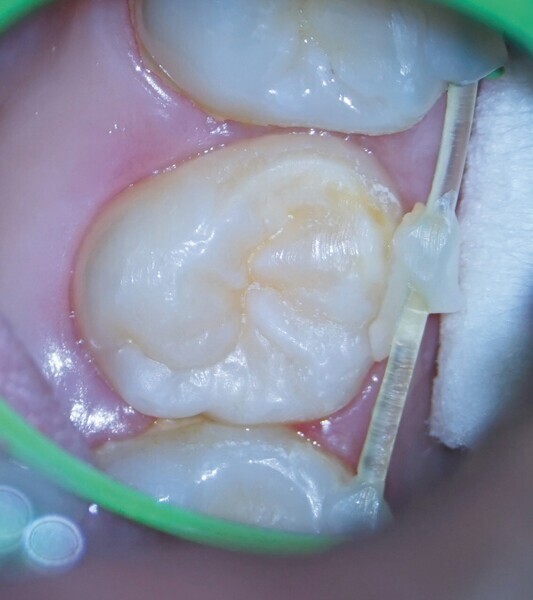

Première molaire maxillaire fortement endommagée, restaurée avec un ancien amalgame après un traitement endocanalaire, et présentant des caries récurrentes. (Photo : Jenner Argueta)

Une patiente de 16 ans a consulté le cabinet pour une évaluation de sa première molaire droite supérieure (dent 16 – Fig. 1). L’orthodontiste qui nous l’avait adressée demandait que tout soit mis en œuvre pour sauver cette dent. Le diagnostic était une parodontite périapicale symptomatique ayant déjà fait l’objet d’un traitement, et un examen minutieux a exclu toute possibilité de restauration. Avec l’accord des parents et de la patiente, nous avons pris la décision d’extraire la dent 16 et de procéder à une transplantation autogène de la dent 18 dans ce site (Fig. 2), étant donné que l’orthodontiste avait déjà prévu l’extraction de cette dent 18 et l’équilibration de l’occlusion de la patiente à la fin du traitement orthodontique. Les dents n 16 et 18 ont été extraites de la manière la moins traumatique possible. Après un remodelage osseux mineur de l’alvéole à l’aide de fraises à basse vitesse, la troisième molaire a été transplantée dans l’alvéole receveuse (Fig. 3). Une contention flexible constituée d’un monofilament de nylon a été utilisée pour maintenir la dent en place (Fig. 4). Deux semaines plus tard, la contention a été retirée, laissant des tissus mous sains et asymptomatiques et une alvéole dans laquelle la dent était stable (Figs. 5a et b).